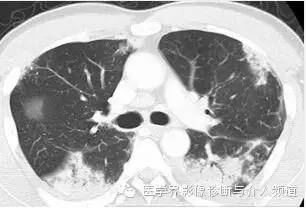

初始CT

初始胸片示两肺野多灶性斑片影,其中两肺上野靠近外周可见边界欠清的实变影,这是典型的慢性嗜酸性粒细胞性肺炎“肺水肿反转影”的表现。CT示两肺叶多灶性非节段性实变影,病变以两上肺周围性分布为主。

CEP的典型影像学表现:普通X线平片为非节段性、分布广泛互相融合的肺泡及间质性实变,病变以中上肺周围性分布为主,表现为“肺水肿反转影”。CT或HRCT表现为一侧或两侧融合性实变、斑片状实变、磨玻璃影、条带状致密影,实变灶与正常肺组织的分界截然清楚。此种典型征象并非见于所有CEP病例。